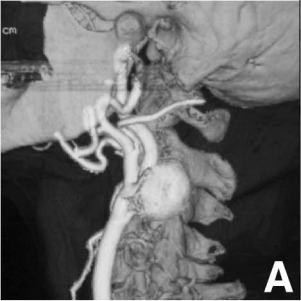

为了查明真相,医生为她安排了详细的血管检查——CT血管造影和MR血管造影。结果清晰地显示:在左侧颈总动脉分叉处,延伸至颈内动脉起始部,藏着一个直径达27mm的囊状动脉瘤!它像一个悄然膨胀的“气球”,随时有破裂的风险(图A)。

3D-CT血管造影显示位于左侧颈动脉分叉处的囊状动脉瘤